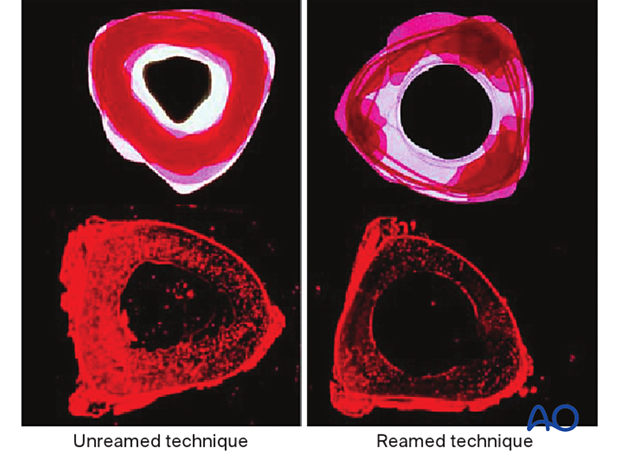

The diameter of the tibial medullary canal varies between 13 mm and 8 mm or less. Reamers can be used to enlarge the medullary canal for larger diameter nails. Such nails permit larger diameter locking screws. The strength and durability of screws and nails increases with their diameter. The medullary canal should be reamed so that it is slightly larger than the intended nail diameter (usually about 1.5 mm more), to ease nail insertion. The image illustrates a non-reamed nail on the left, and a reamed nail on the right. Stability is increased with the reamed technique, because the nail fits snugly in a longer portion of the tibial shaft.

Reaming damages the medullary blood supply and causes temporary thermal necrosis of the diaphyseal bone. Theoretically, this increases the risk of infection, which may be relevant for open fractures. Clinical studies have not demonstrated this.

Studies have shown increased union of tibial shaft fractures using reamed compared to unreamed intramedullary nails.

Non-reamed nailing was initially developed to theoretically reduce the risks of infection and pulmonary dysfunction from embolized medullary debris. These benefits have not been shown to be clinically significant. Since smaller diameter, “non-reamed” nails are mechanically weaker, particularly with regard to smaller locking screws, their reoperation rate is higher.